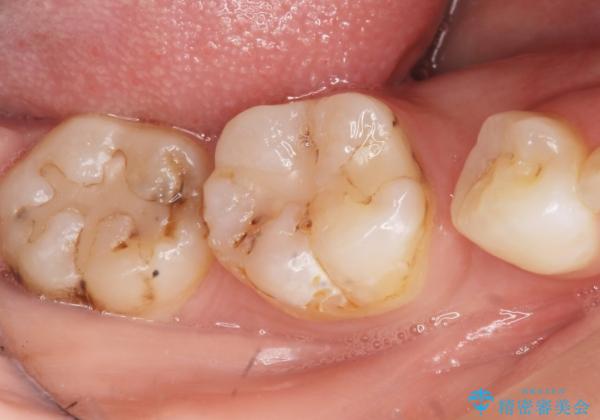

矯正せずに早く治したいという強いご希望とう蝕があることから、セラミッククラウンによる補綴治療で隙間を閉じることにしました。

- ¥242,000 (仮歯・クラウン×2本) ※税込費用は治療当時の料金となります

クラウンの種類:オールセラミッククラウン スタンダード